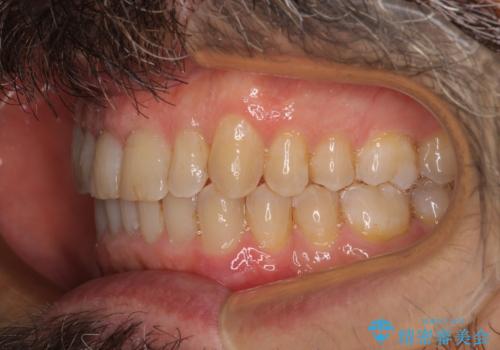

- 前歯のデコボコを気にして来院された患者様です。

インビザラインでもワイヤー装置でも対応可能でしたが、仕事の都合で来院回数を減らしたいとのことでインビザラインによる矯正治療を選択されました。

著しく咬合力が強いため、奥歯がしっかりと噛めずに治療が長引くことが懸念されました。

1セット目のインビザラインを使用した際には左右ともに大臼歯が咬み合っていなかったのですが、2セット目できっちりと仕上げることができました。